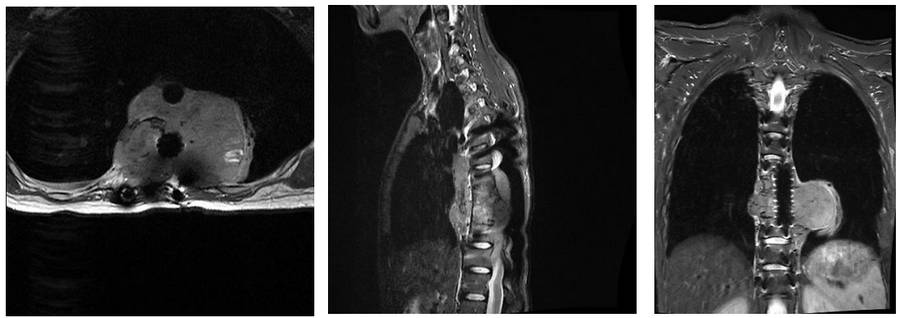

Ameliyat öncesi: MR’da büyük boyutta tümör nüksü görülmekte